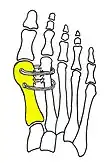

Syndesmosis procedure addresses specifically the two fundamental problems of metatarsus primus varus deformity that gives rise to the bunion deformity. They are leaning and instability of the first metatarsal bone . Syndesmosis procedure uprights the leaning first metatarsal bone with strong binding sutures between it and the second metatarsal bone (Fig. 2) and then also stabilizes it uniquely by creating a fibrous connecting bridge between these two bones (Fig. 3, 4). First metatarsal bone can be readily realigned because by definition of the metatarsus primus varus deformity its first metatarsal is abnormally loose and mobile.